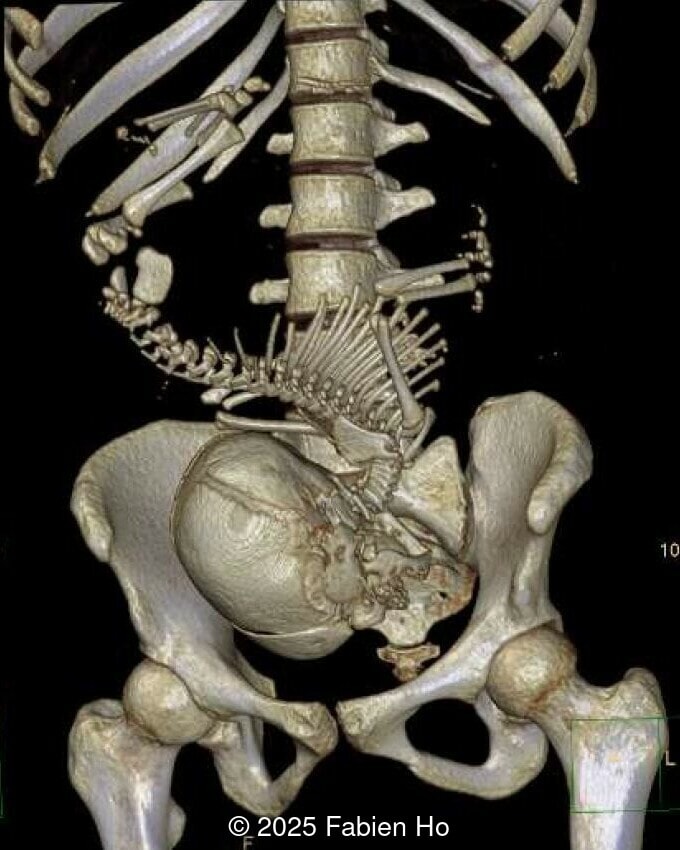

At 36 weeks gestation, the abdominal findings were unchanged however, the bones appeared short (<1st percentile) and the spine had an unusual appearance, therefore a computed tomography was performed at 37 weeks gestation.

• Short long bones (<1st percentile), normal mineralization, and no sign of lethal chondrodysplasia

• Dysostosis: Hemivertebrae L3, fused L4-L5, abnormal left foot with short metatarsals and missing phalanges

The couple chose to deliver naturally. After prenatal needle aspiration of the bladder, the baby was delivered at 39 weeks gestation. Postnatal findings were consistent with Prune-Belly Syndrome with flaccid abdominal wall (similar to prune skin), lower urinary tract obstruction in a male fetus, imperforate anus requiring colostomy, lumbar hemivertebrae, and left foot hypoplasia including metatarsals and phalanges.